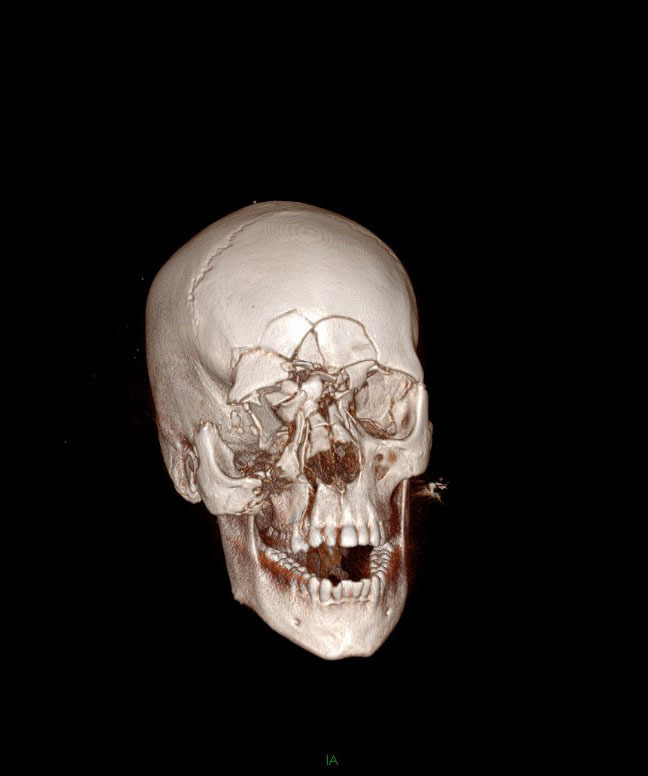

Question 4 - Il n’y a pas d’urgences neurochirurgicales sur le scanner (pas d’hématome intracrânien ni de brèche ostéoméningée). Voici les clichés de reconstruction 3D. Figure 2Figure 3Figure 4

Il y a une fracture complexe des OPN, qui s’intègre d’ailleurs dans une fracture CNEMFO

On retrouve une fracture verticale de l’hémi-maxillaire droit

Le zygoma droit est complètement détaché du bloc osseux facial. Le gauche est normal

Il n’y a aucun trait de fracture sur la mandibule

Il y a une fracture centro-faciale importante

Il y a plusieurs fractures faciales chez ce patient. On retrouve en premier lieu une fracture du CNEMFO, ainsi que deux autres fractures : fracture du zygoma droit et fracture verticale du maxillaire droit.

Rappel sur le CNEMFO : une fracture du complexe naso-éthmoïdo-maxillo-fronto-orbitaire fait suite à un choc de haute vélocité centro-facial. Le point d’impact pourrait correspondre à une fracture des os propres du nez (OPN), mais l’importance du choc entraîne un écrasement complet de la pyramide nasale et une fracture des os environnants : l’os frontal vers le haut, l’orbite (paroi médiale et plancher), la branche montante du maxillaire, et l’os éthmoïdal en arrière. Lorsque la fracture est isolée, il n’y a pas d’atteinte du zygoma.